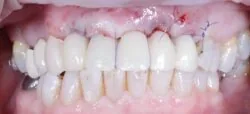

Tissue level implants: the result

This case beautifully demonstrates the emergence profile that the tissue level implants facilitate along with the ease of cleansability for the patient, even when the prosthesis is placed posteriorly in difficult to reach areas.